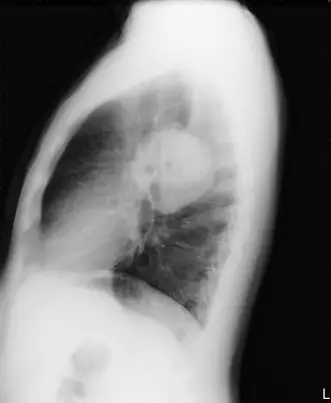

側位胸部X光片

- 該陰影位於後基底部,投影方向圓形,並非沿肺葉間裂而呈雙凸透鏡狀(lenticular)的葉間積液假腫瘤(pseudotumor)特徵 (radiology.az)。